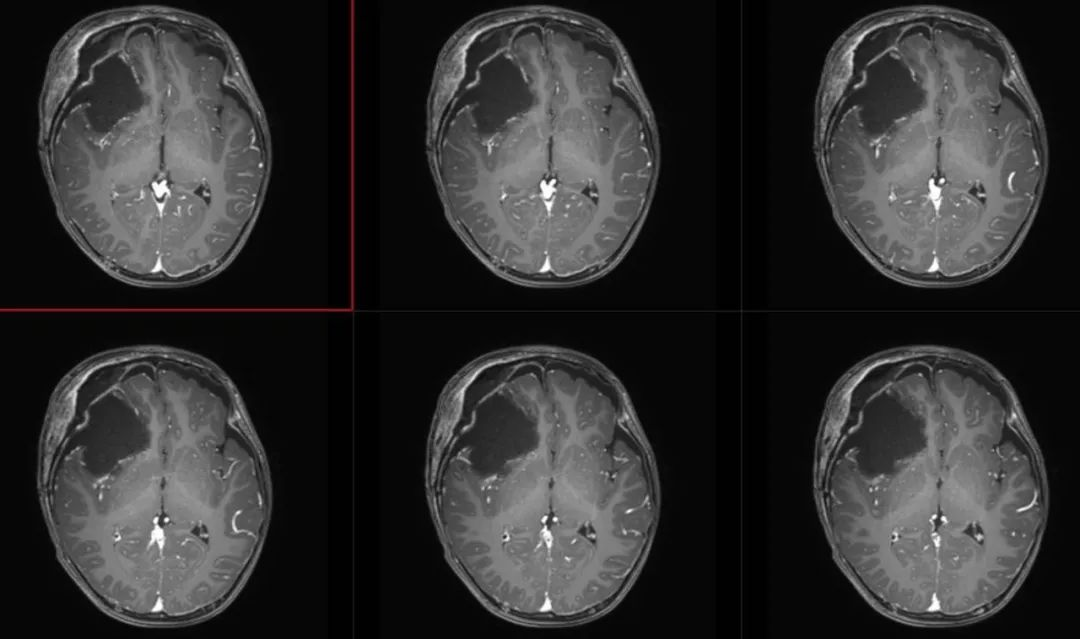

术前影像

术前颅脑CT囊实性占位

术前T1轴位

术前T1冠状位

术前FLAIR

术前T2轴位

术前T2矢状位

术前颅脑MRA、MRV

术前T1冠状位增强

术前T1轴位增强

术后复查

术后第1天头颅CT

术后第3天T2

术后FLAIR

术后T1冠状位增强

术后T1矢状位增强

术后T1轴位增强